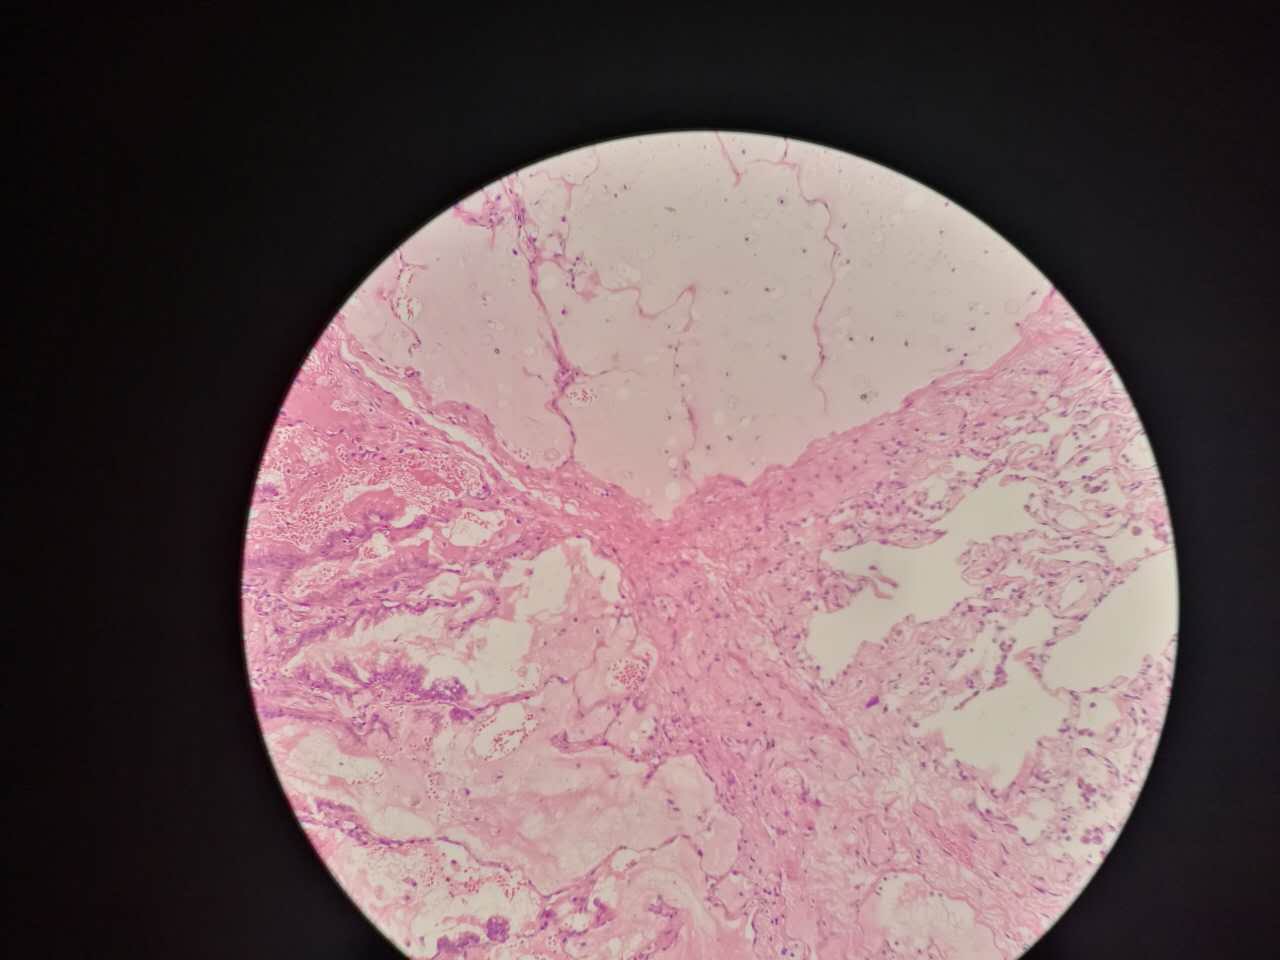

也会有些坏死,连同粘液咳出去,就形成实变区内的空洞

鳞癌

左手边有一点鳞癌,右手边有正常肺泡组织,中间有坏死物,这是为什么呢?

坏死物质渗出。

并且可以有吞噬,坏死物里常有血液成分

剖面多呈黄色

肿瘤周围不应是缺血,坏死一般在巢团内